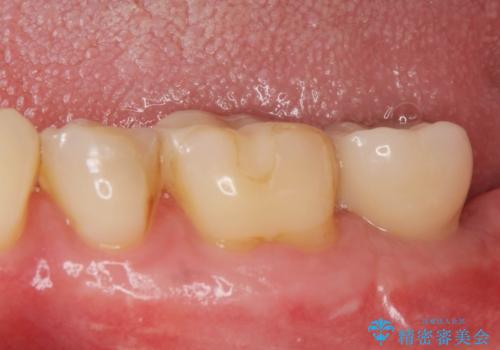

歯の抜去を行い、骨の造成を含めたインプラントによる咬合機能の回復を図ります。

- 44万円(インプラント・チタンカスタムアバットメント・ジルコニアクラウン・仮歯)費用は治療当時の料金となります